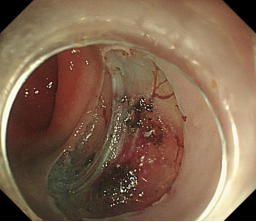

胃内粘膜下隆起,术前超声提示来源于固有肌层,术前判断需胃壁全层切除。

术中所见与术前判断相符,行内镜全层切除术EFTR,术后严密封闭创面,患者2日后安全出院,术后病理诊断胃间质瘤。